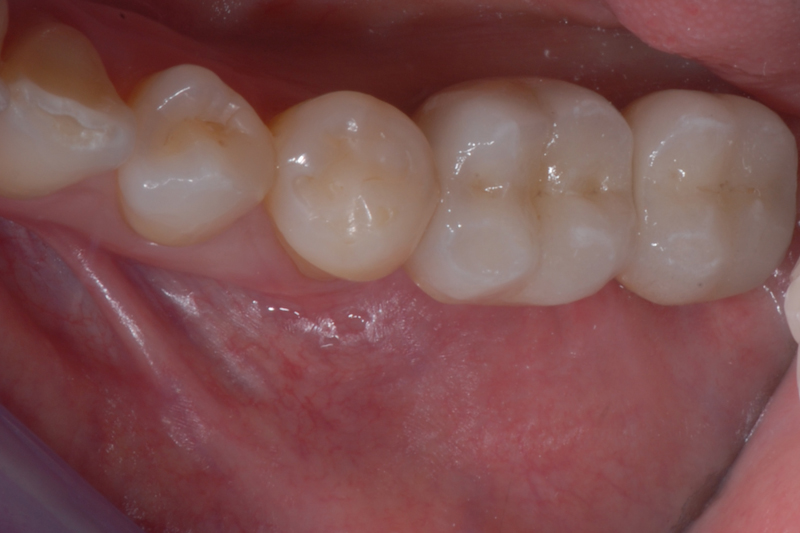

- Status kliniczny po wprowadzeniu odbudowy protetycznej

- status kliniczny po wprowadzeniu odbudowy protetycznej – widok powierzchni okluzyjnej